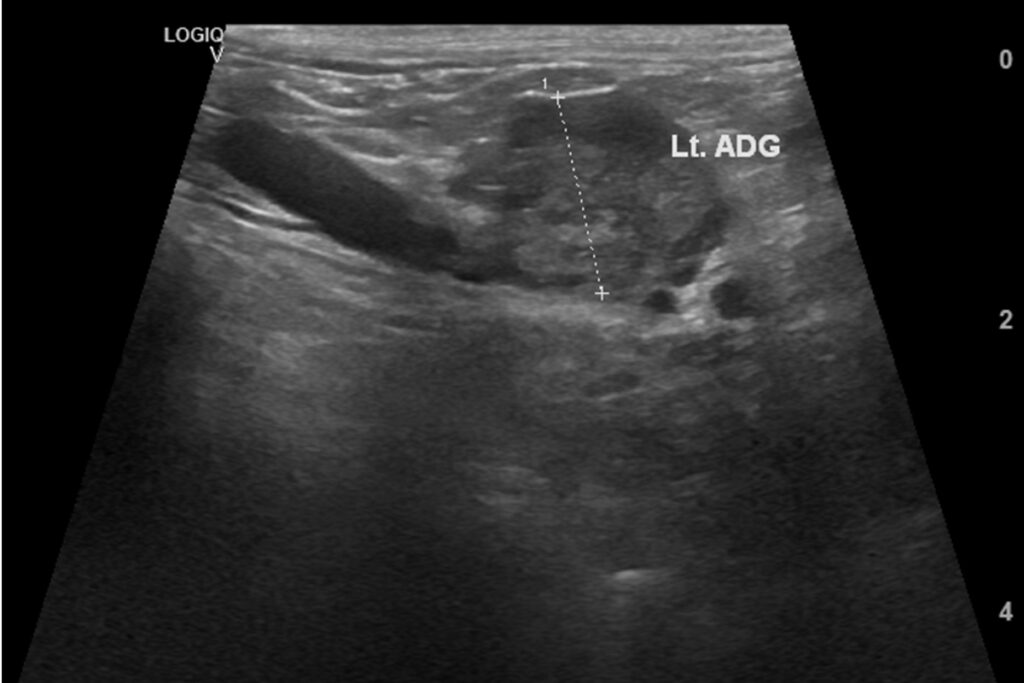

쿠싱증후군

부신 호르몬 과다 분비로 인해 다음, 다뇨, 복부 팽만, 근육 감소 등이 나타날 수 있는 질환입니다.

장기적인 호르몬 조절과 세심한 모니터링이 필요합니다.